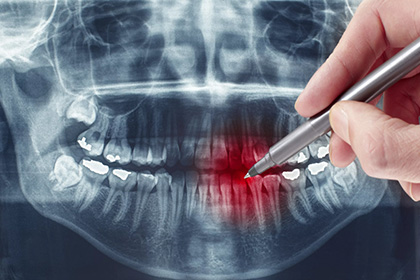

- После травм челюстно-лицевого отдела

- Диагностика воспалений и новообразований

- Для оценки состояния корней

- Установка имплантов